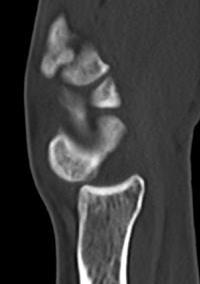

Lateral xray

Distal radius / lunate / capitate: not aligned, spilled teacup

Normal versus spilled tea cup appearance on lateral with spilled tea cup

CT

Trans-scaphoid perilunate dislocation

Perilunate dislocation